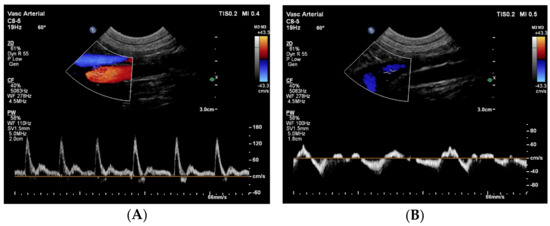

Next, an abdominal ultrasound examination was performed to investigate the abdominal aorta and the CVC. The abdominal aorta showed normal pulsed-wave Doppler flow pattern, but unexpectedly, it was located to the right of the CVC (Figure 2).

Figure 2. Duplex Doppler images of the abdominal aorta (A) and the caudal vena cava (B) caudal to the kidneys show normal spectral flow pattern in both vessels using pulsed-wave Doppler technique, but an abnormal anatomical localization, as the caudal vena cava (blue) is located to the left of the aorta (red). These images were obtained from the left lateral abdomen with the dog in right lateral recumbency. On both images left is cranial, right is caudal, top is left and bottom is right. With a normal aortic flow pattern, aortic coarctation was excluded.